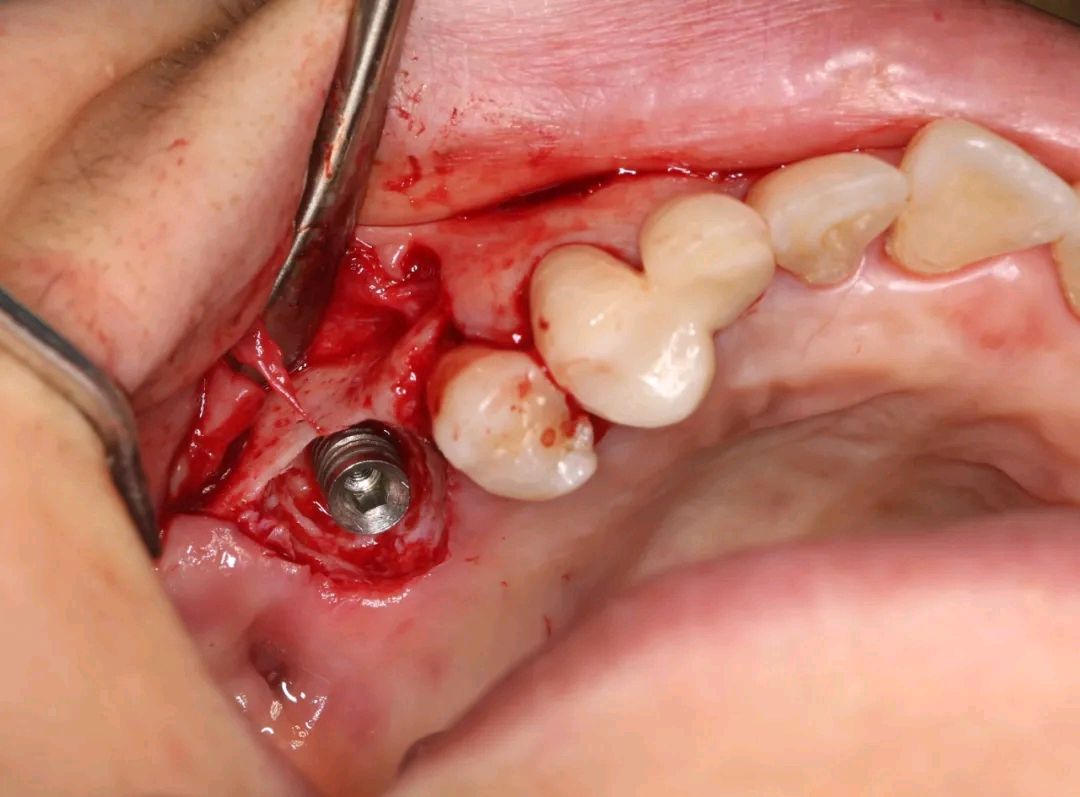

3、16翻瓣术彻底清创 暴露的种植体表面及周围

发现种植体颈部典型弹坑状骨破坏,同期行引导种植体周围骨再生术(GBR 技术)。